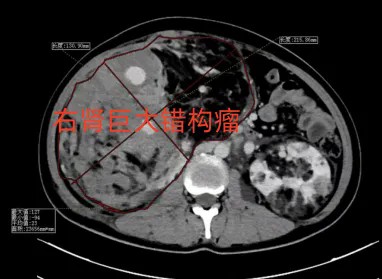

在抢救治疗的同时,急诊医学科值班医护团队仔细评估、完善辅助检查发现,W女士患有罕见的“结节性硬化症”,这是一种常导致全身多器官(如脑、肾、皮肤等)发生良性肿瘤(错构瘤)的遗传性疾病。患者既往有癫痫病史,且5年前曾有过肾错构瘤出血保守治疗史。此次出血的“元凶”正是其右肾一个巨大的血管平滑肌脂肪瘤(即肾错构瘤)发生破裂所致。由于瘤体体积巨大、血供异常丰富且出血凶猛,在当地医院保守治疗无效。腹部CT也证实,患者右肾已被一个约25cm×25cm、占据大半腹腔的巨大瘤体占据并严重变形,正常肾组织几乎被完全挤压取代,腹腔多发扩张迂曲血管影,腹盆腔渗出、积液,情况复杂。若直接进行外科切除手术,术中大出血风险极高,患者很可能无法耐受。